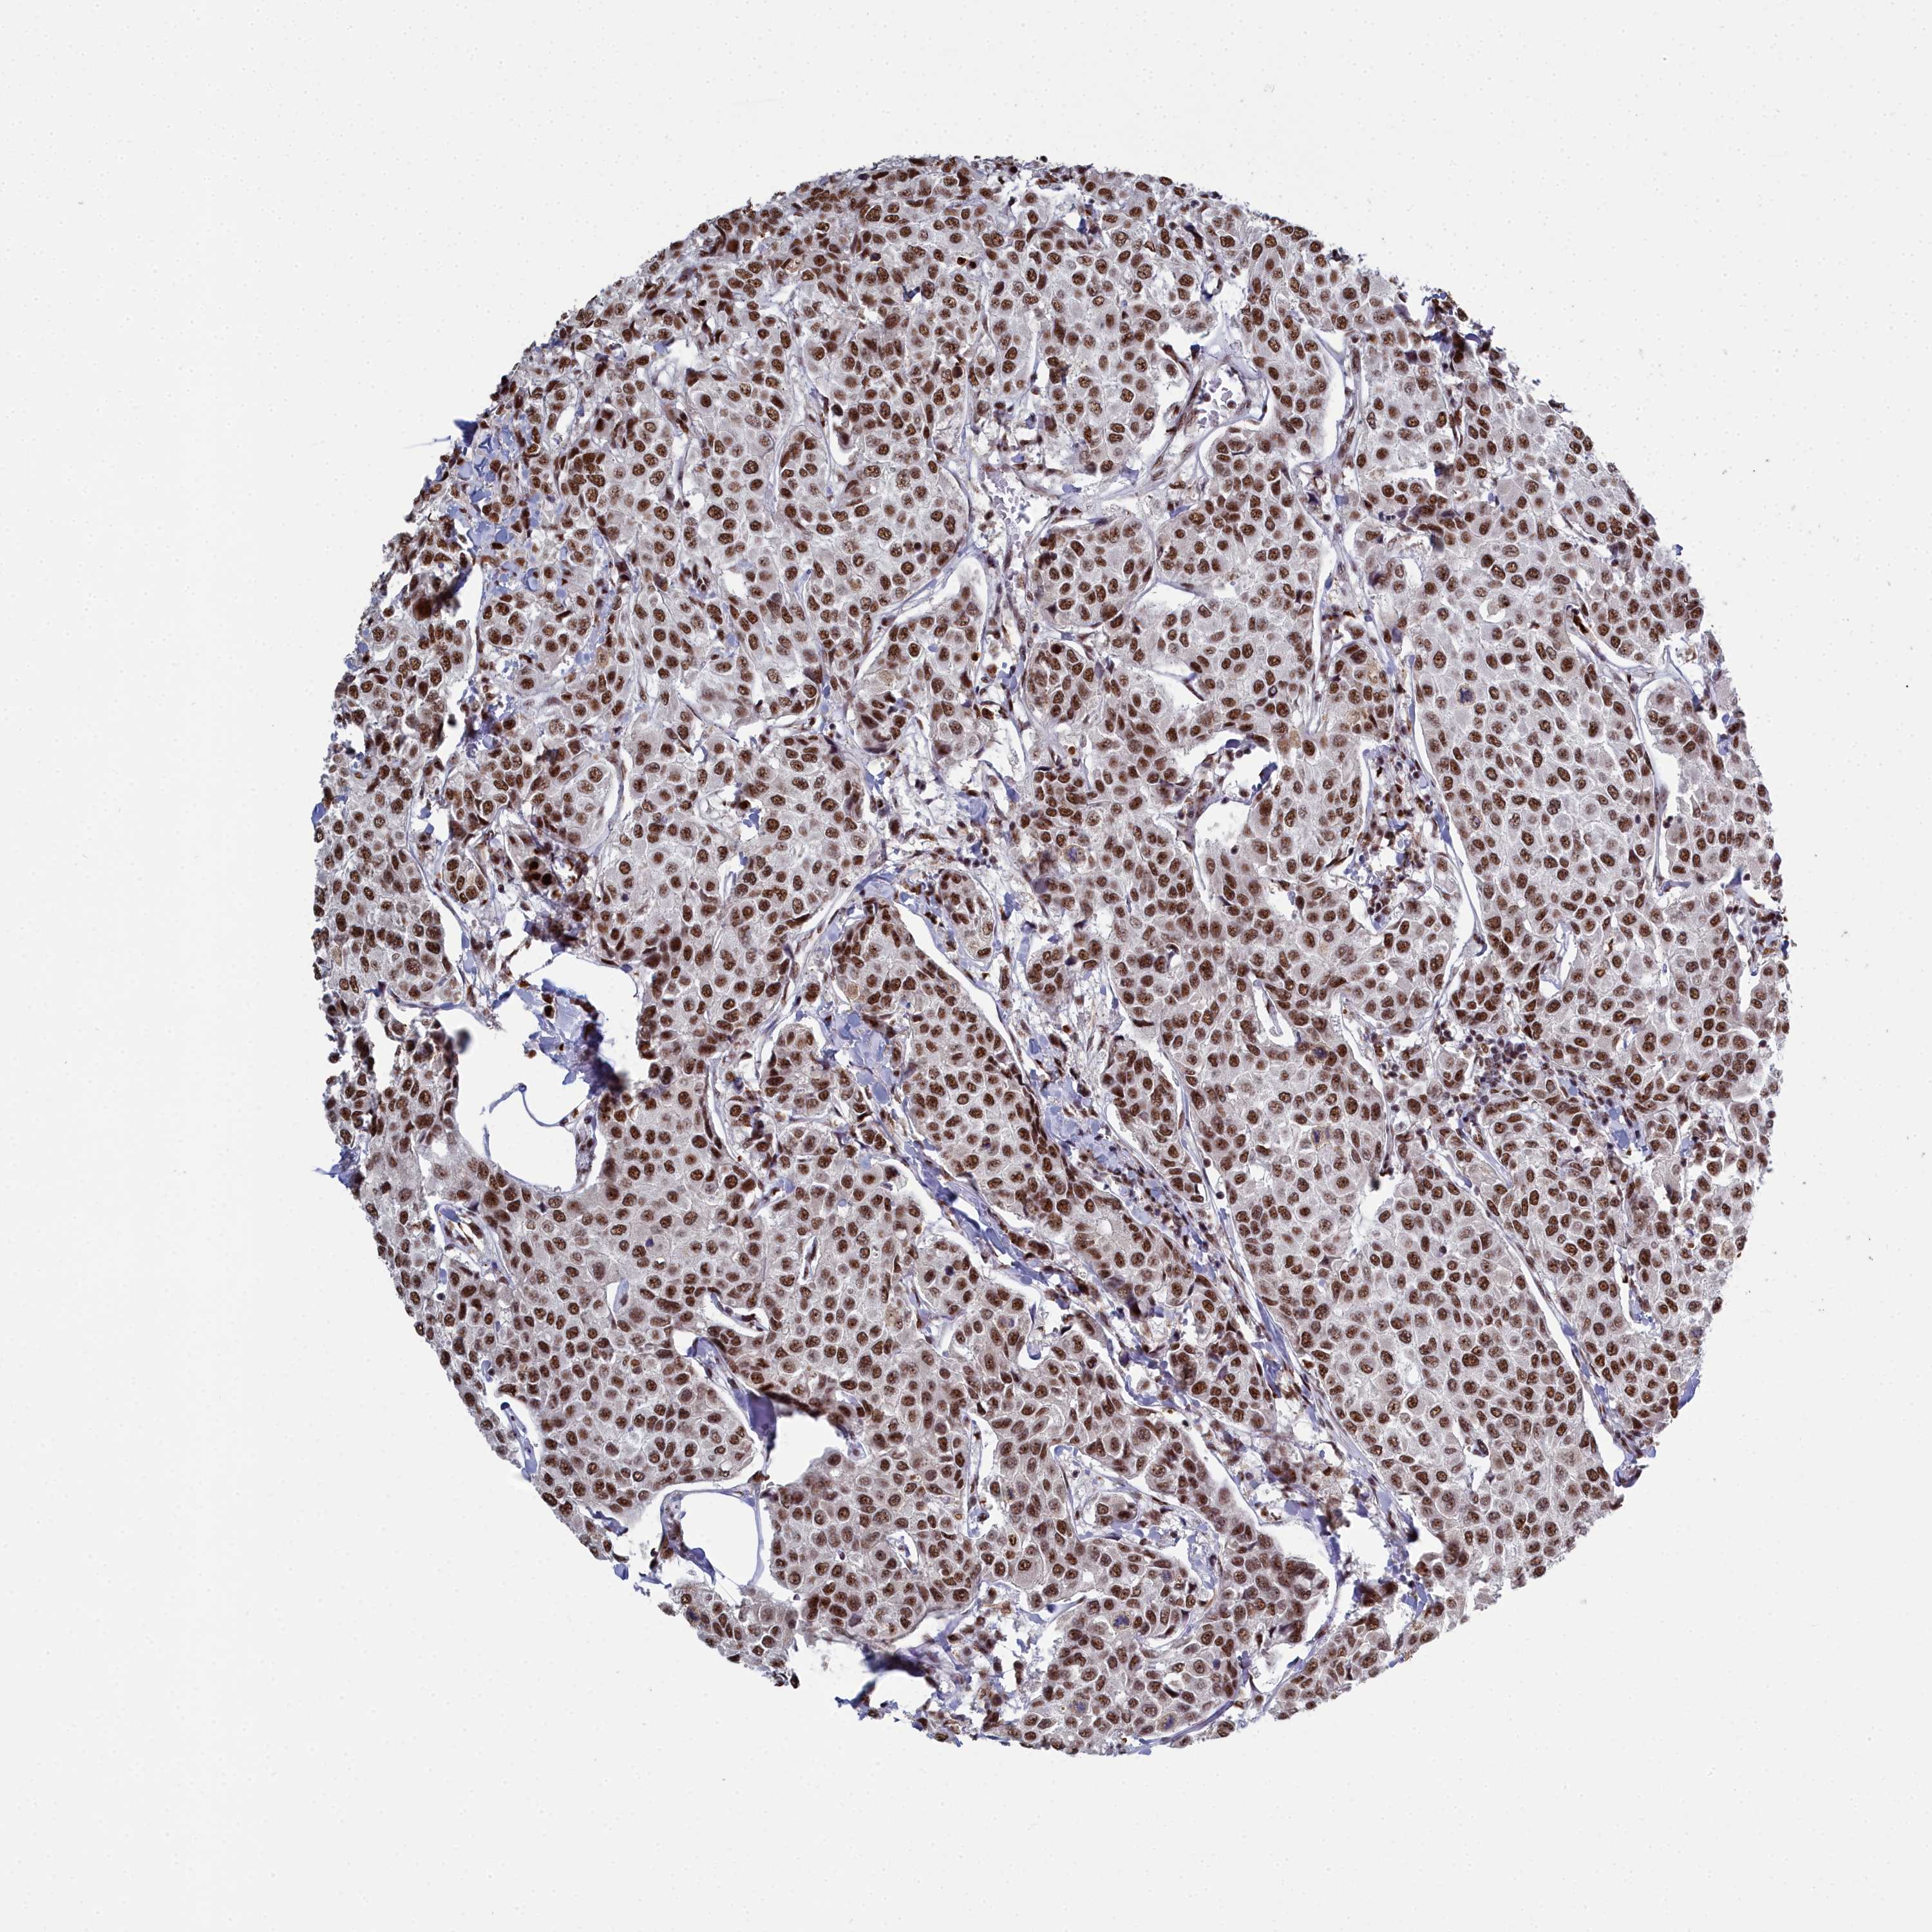

CANCER BREAST CANCER Show tissue menu

BRCA TCGA BRCA VALIDATION PROTEIN EXPRESSION

Breast cancer

Human cancer